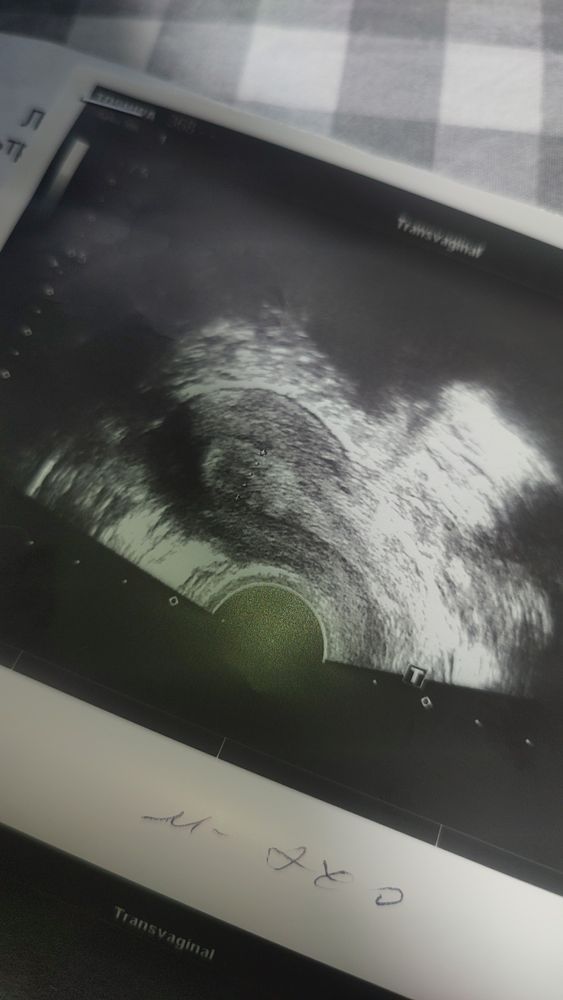

19 мм хороший фолликул. Может совулировал, либо это еще впереди. Уже 23 дц, а цикл у вас длинный вообще? Похоже на позднюю овуляцию. Но жидкость может по разным причинам быть, не только от овуляции. Тут непонятно. Переделайте узи через пару дней.

Ника, вообще происходит на 18-19 ДЦ,но в том цикле была на 26

Могло просто еще не сформироваться, часто такое бывает, что видят жидкость, а ЖТ нет. ЖТ формируется по разному, у кого-то сутки, а у кого-то на 3-4 день после овуляции только его видно.

Скорее всего в момент овуляции были. Фолликул только надорвался, фолликулярная жидкость вышла, а желтое тело еще не сформировалось. Повторите УЗИ через 2 дея